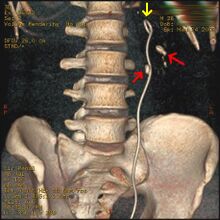

Otherwise a noncontrast helical CT scan with 5 millimeters (0.2 in) sections is the diagnostic method to use to detect kidney stones and confirm the diagnosis of kidney stone disease.[16][56][60][65][7] Near all stones are detectable on CT scans with the exception of those composed of certain drug residues in the urine,[58] such as from indinavir.

Axial CT scan of abdomen without contrast, showing a 3-mm stone (marked by an arrow) in the left proximal ureter

Ureteroscopy has become increasingly popular as flexible and rigid fiberoptic ureteroscopes have become smaller. One ureteroscopic technique involves the placement of a ureteral stent (a small tube extending from the bladder, up the ureter and into the kidney) to provide immediate relief of an obstructed kidney. Stent placement can be useful for saving a kidney at risk for postrenal acute kidney failure due to the increased hydrostatic pressure, swelling and infection (pyelonephritis and pyonephrosis) caused by an obstructing stone. Ureteral stents vary in length from 24 to 30 cm (9.4 to 11.8 in) and most have a shape commonly referred to as a "double-J" or "double pigtail", because of the curl at both ends. They are designed to allow urine to flow past an obstruction in the ureter. They may be retained in the ureter for days to weeks as infections resolve and as stones are dissolved or fragmented by ESWL or by some other treatment. The stents dilate the ureters, which can facilitate instrumentation, and they also provide a clear landmark to aid in the visualization of the ureters and any associated stones on radiographic examinations. The presence of indwelling ureteral stents may cause minimal to moderate discomfort, frequency or urgency incontinence, and infection, which in general resolves on removal. Most ureteral stents can be removed cystoscopically during an office visit under topical anesthesia after resolution of urolithiasis.[114] Research is currently uncertain if placing a temporary stent during ureteroscopy leads to different outcomes than not placing a stent in terms of number of hospital visits for post operative problems, short or long term pain, need for narcotic pain medication, risk of UTI, need for a repeat procedure or narrowing of the ureter from scarring.[115]